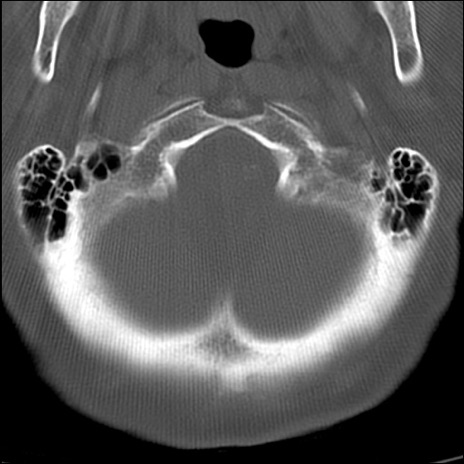

症例48 頚椎CT(横断像)

頚椎CT